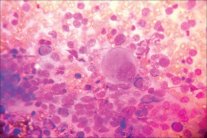

نشرت المجلة الطبية البريطانية (BMJ) دراسة حديثة أجريت على عدد من مرضى السكري من النوع الثاني اللذين يتناولون دواء بيوجليتازون خافض لسكر الدم، وتبين أن هذا النوع من الدواء يزيد من خطر الإصابة بسرطان المثانة بنسبة ٦٣ في المئة.

وتمت مراقبتهم ومتابعتهم حتى تموز (يوليو) ٢٠١٤، وتبين أن ٦٢٢ من هؤلاء المرضى يعانون سرطان المثانة، ولم يعثر على أي خطر متزايد لدواء روزيجليتازون، لكنه تم سحبه من السوق في عام 2010، لأنه يزيد من خطر الإصابة باضطرابات القلب والأوعية الدموية، بما في ذلك النوبات القلبية وقصور القلب.